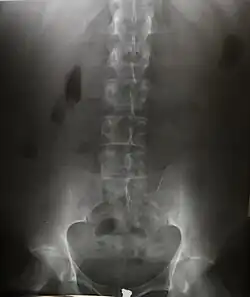

Since the body is made up of various substances with differing densities, ionising and non-ionising radiation can be used to reveal the internal structure of the body on an image receptor by highlighting these differences using attenuation, or in the case of ionising radiation, the absorption of X-ray photons by the denser substances (like calcium-rich bones). The discipline involving the study of anatomy through the use of radiographic images is known as radiographic anatomy. Medical radiography acquisition is generally carried out by radiographers, while image analysis is generally done by radiologists. Some radiographers also specialise in image interpretation. Medical radiography includes a range of modalities producing many different types of image, each of which has a different clinical application.

Projectional radiography

The creation of images by exposing an object to X-rays or other high-energy forms of electromagnetic radiation and capturing the resulting remnant beam (or "shadow") as a latent image is known as "projection radiography". The "shadow" may be converted to light using a fluorescent screen, which is then captured on photographic film, it may be captured by a phosphor screen to be "read" later by a laser (CR), or it may directly activate a matrix of solid-state detectors (DR—similar to a very large version of a CCD in a digital camera). Bone and some organs (such as lungs) especially lend themselves to projection radiography. It is a relatively low-cost investigation with a high diagnostic yield. The difference between soft and hard body parts stems mostly from the fact that carbon has a very low X-ray cross section compared to calcium.